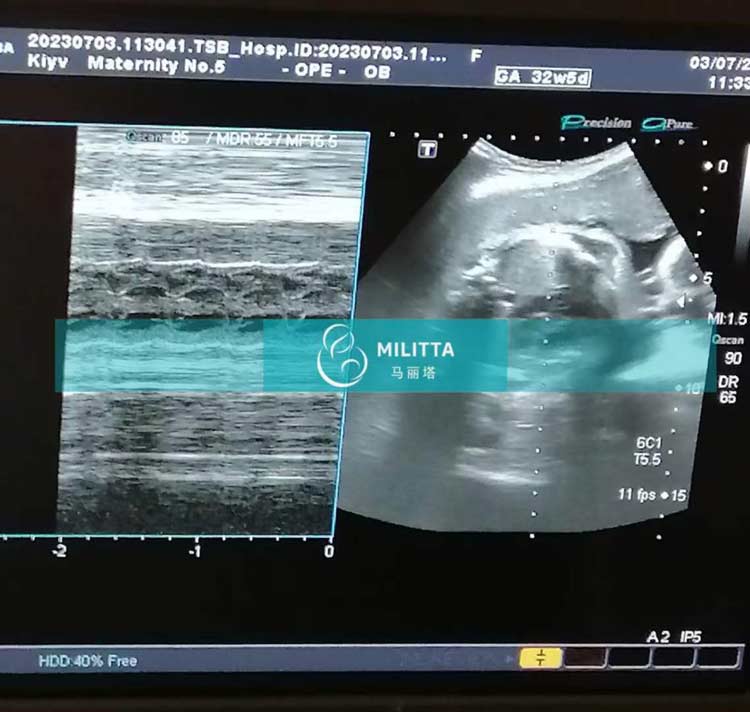

来妇产医院做B超孕检的三位乌克兰试管妈妈

来妇产医院做B超孕检的三位乌克兰试管妈妈,其中一位孕中期,两位孕晚期,胎宝宝们都发育的很好,期待着TA们的到来